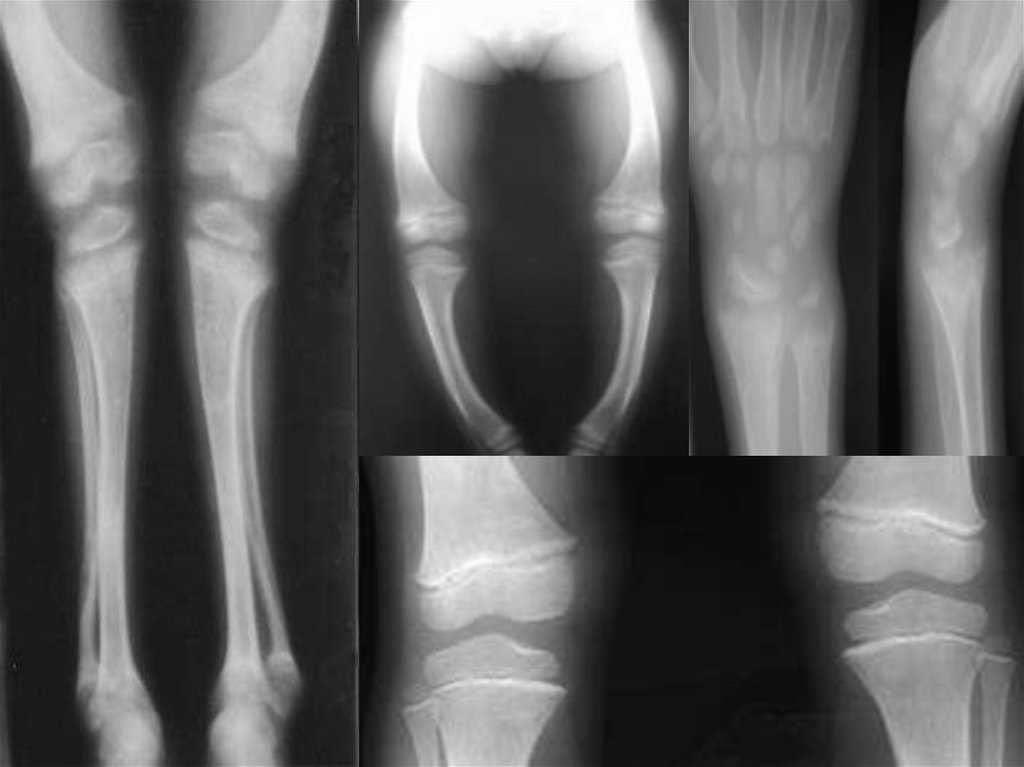

3. Рентгенограмма костей скелета – остеопороз.

12. III степень

Деформация костей черепа, грудной клетки, позвоночника

+ разнообразные изменения трубчатых костей:

a) верхние конечности:

искривление плечевой кости и костей предплечья;

Деформация в области суставов: «браслеты» (утолщение в

области лучезапястных суставов), «нити жемчуга»

(утолщение в области диафизов фаланг пальцев).

б) нижние конечности:

искривление бедер вперед и кнаружи;

разнообразные искривления нижних конечностей (О- или

Х- образные деформации,);

деформации в области суставов.